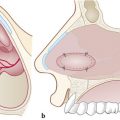

The perforation margins are then bilaterally trimmed and widely detached all around the perforation from the underlying cartilage or bone by a sickle knife to achieve a “refreshening of the edge” (Fig. 19‑1). It is important to elevate bilaterally an area of mucoperiosteum or mucoperichondrium of at least 1 cm all around the perforation.

Through a hemitransfixion incision, mucoperichondrial and mucoperiosteal layers are extensively elevated on one side of the nasal septum, from the inferior edge of quadrilateral cartilage up to the choana, nasal floor, and 1 cm from the nasal roof (Fig. 19‑2).